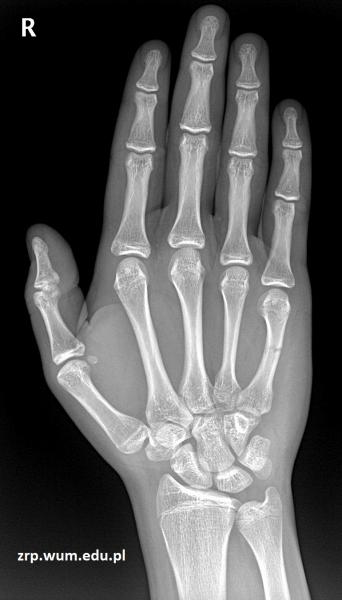

16-latek po urazie śródręcza prawego

Przypadek 61: 16-latek po urazie śródręcza prawego - przypadkowe uderzenie w słup.

Rozpoznanie: Złamanie środkowej części trzonu 5-ej kości śródręcza, z ugięciem odłamu dystalnego.